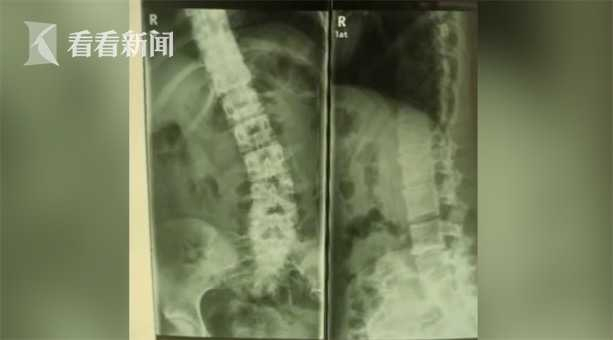

哈医大一院骨科五病房主任王岩松表示:“经过检查我们发现她有一个巨大的腰间盘突出,腰椎侧弯是由腰间盘突出引起的,是代偿性的。”

腰间盘突出?那不是中老年人才会得的病吗?俗话说,伤筋动骨一百天,他们希望能用保守治疗的方式治好小迪的病。可尝试了很多办法,都于事无补。孩子的病情不但没有好转,反而越来越严重,小迪的父母最终决定听从医生的建议,给小迪做手术。

哈医大一院 骨科五病房主任王岩松解释:“我们通过微创的技术,七到十毫米的一个小口,突出的间盘拿掉以后,姿势就恢复了,腰疼和腿疼的症状就消失了。”